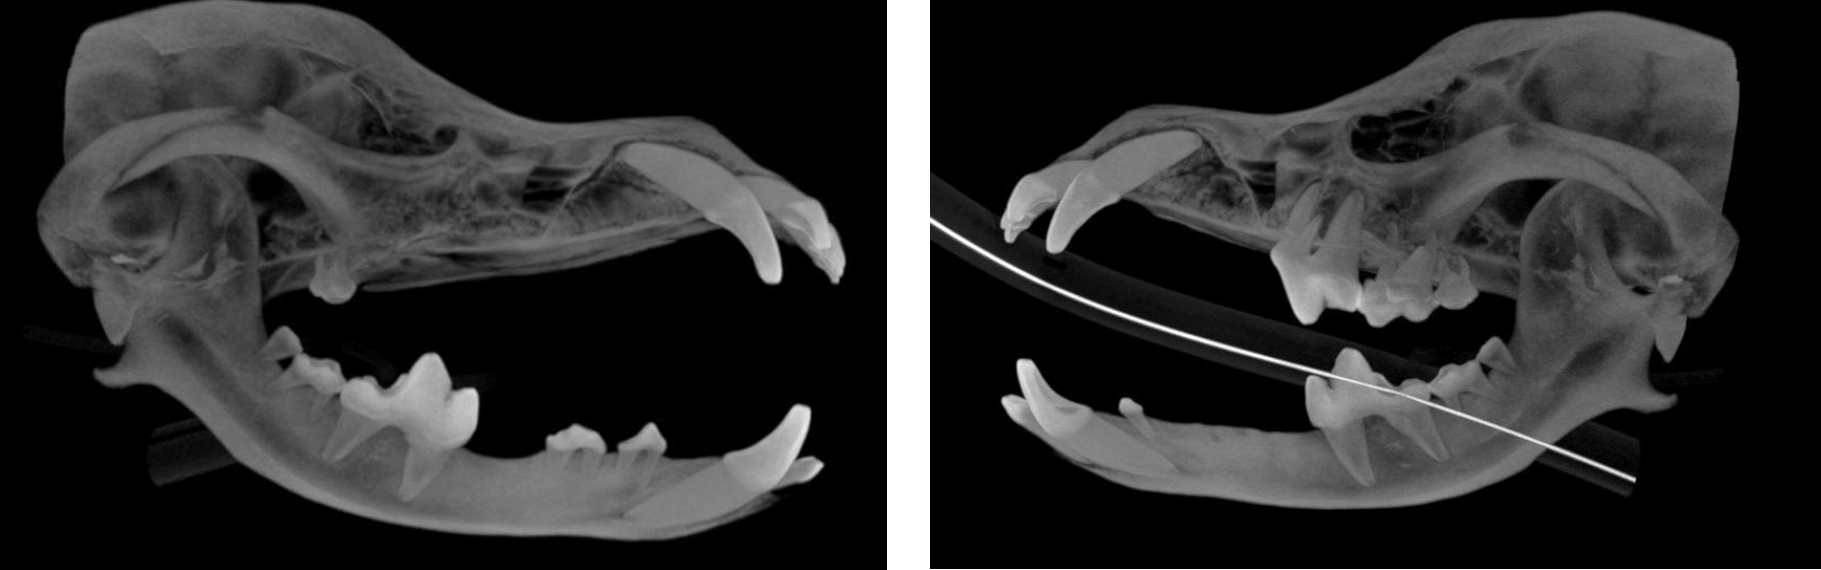

Below: CBCT Hard tissue reconstruction

Below: High intensity CBCT Image

Below: Bone loss affecting upper left canine tooth